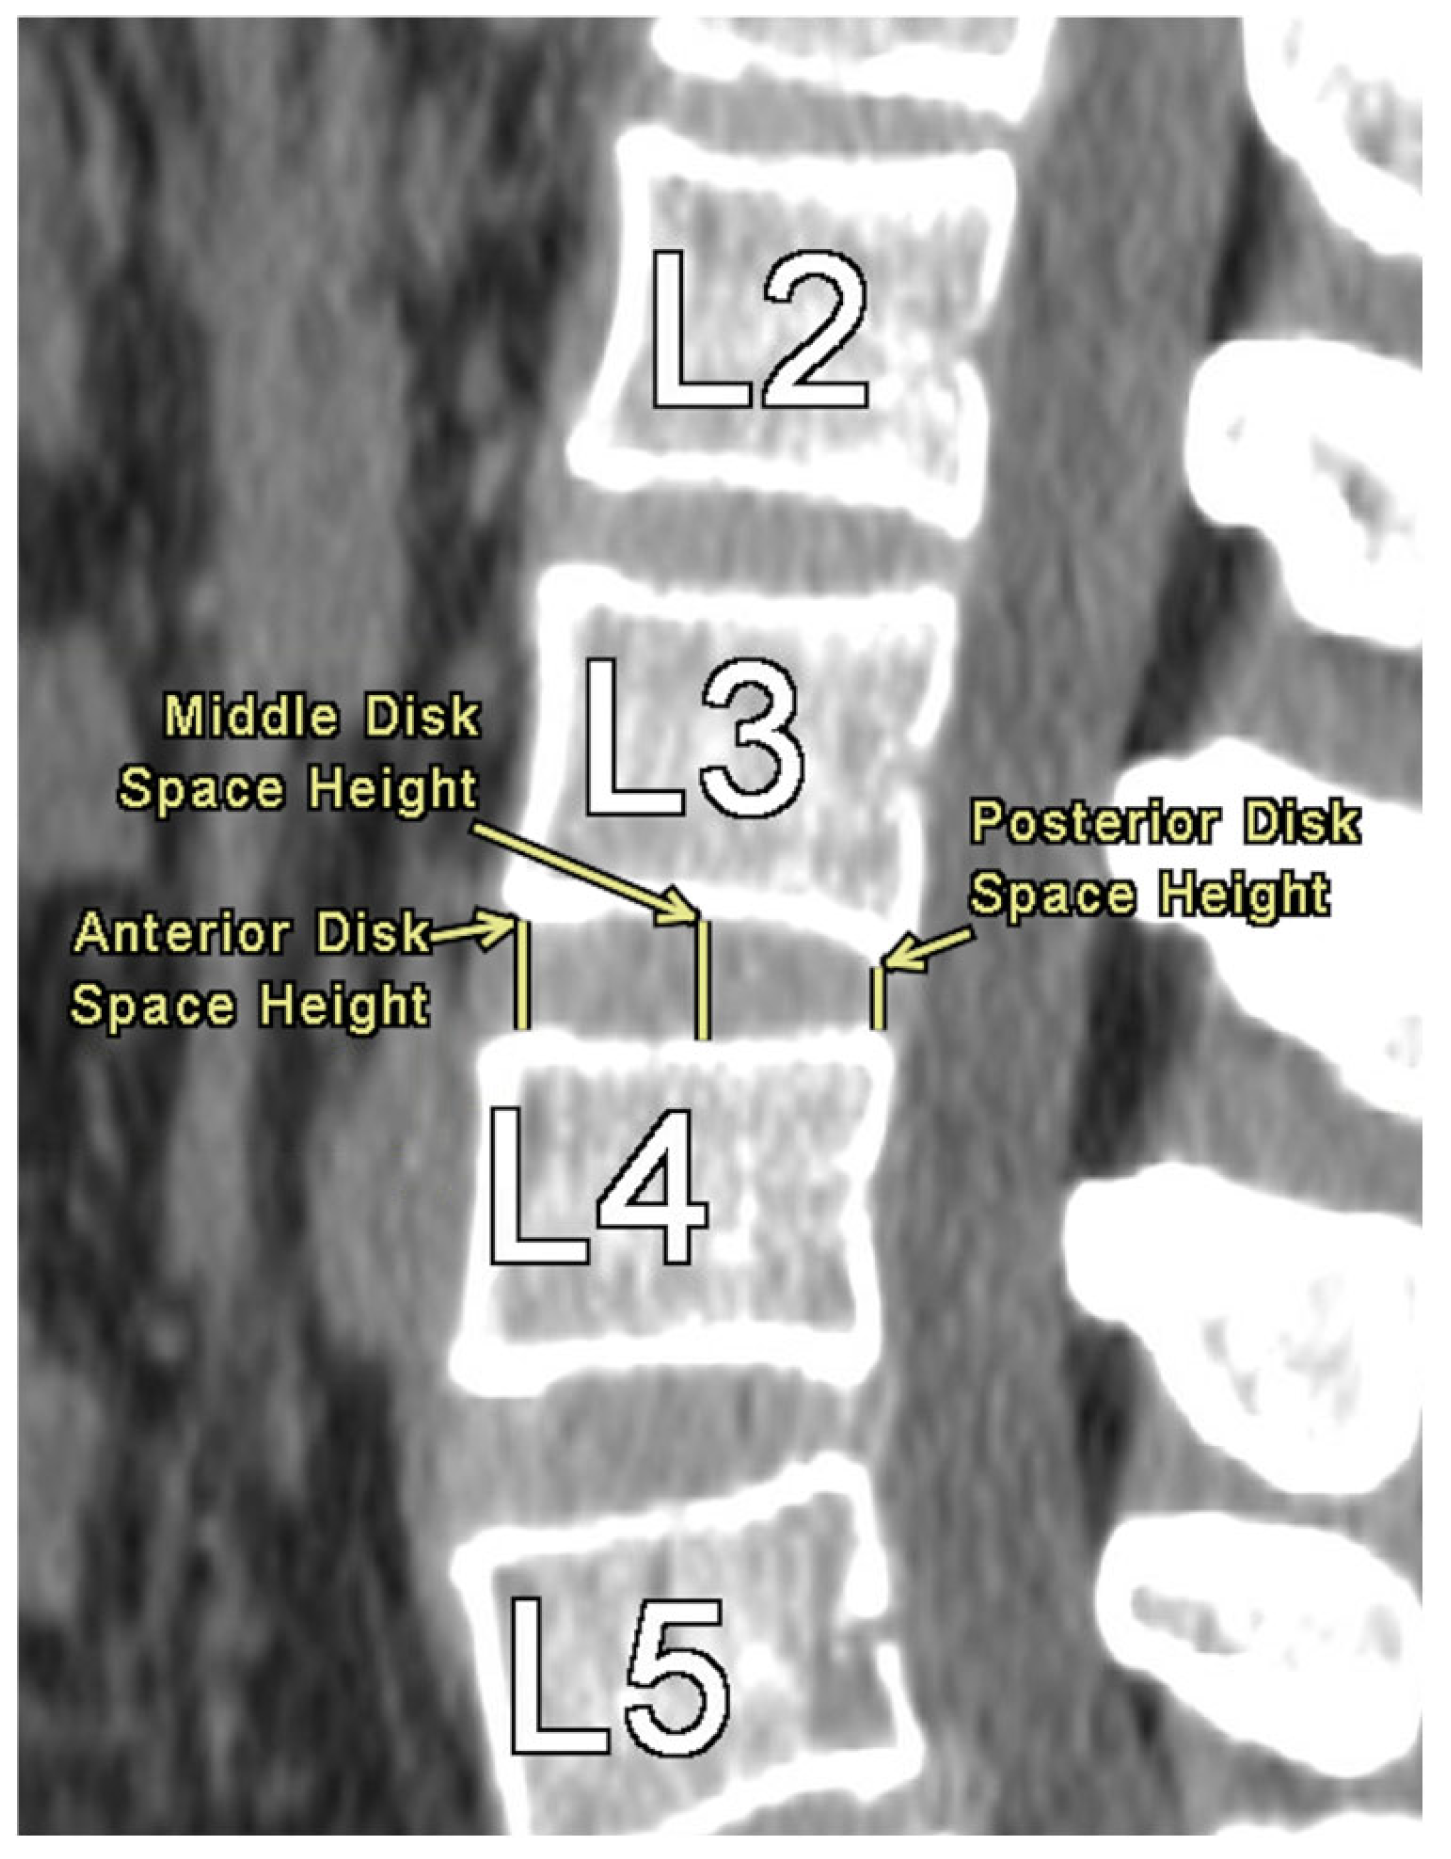

The authors took axial and sagittal CT imaging measurements and first located the midline of the lumbar spine in both views. Then, the measurements were taken at each level from L1 to L5. Figure 1 provides an illustration of the measurement technique for ISD, measured as the shortest vertically linear distance between the most caudal tip of the superior spinous process down to the top of the inferior spinous process in the mid-sagittal plane. DSH was measured between each vertebra using sagittal CT views and recorded in the mid-sagittal plane anteriorly, at the middle, and posteriorly. These distances were defined as the shortest vertical distances between the superior and inferior endplates at their respective vertebra, as illustrated in Figure 2.

Figure 2. Disc Space Height Measurement at L3-L4.